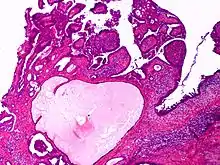

النوع الحليمي من سرطانة الغدة المفترزة